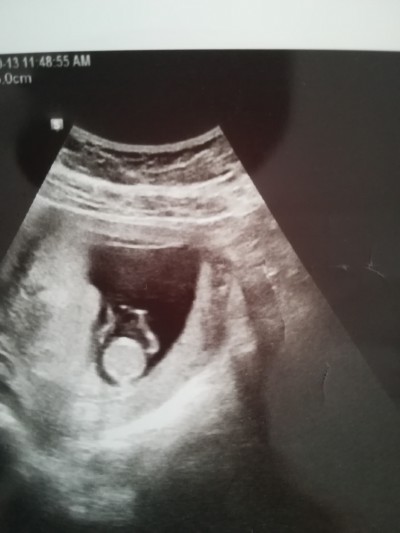

Gebelik haftası 11+5

İkinci gebelik ilki erkek sağlıklı olsun da insan merak içinde

Bacaklar yukarda ise erkek.